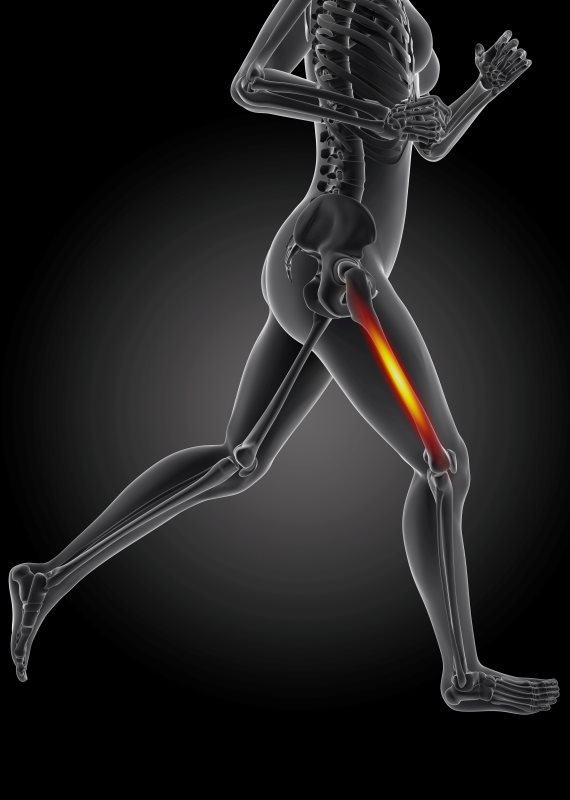

לא סוחבת

"לפני מספר חודשים נפלתי ושברתי את האגן ועכשיו אני מרגישה שהרגלים שלי חלשות"

24/11/2017